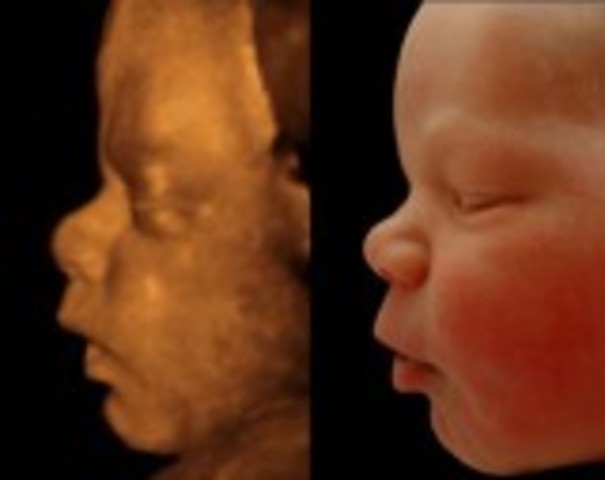

The fetus' facial features are more pronounced, eyes move closer inward, nose is sticking out more, and it's ears are more developed. The fetus will start urinating into the surrounding amniotic fluid because of the kidneys development. The fetus is 3.5 inches long and weights 1.5 ounces, ovaries start moving into place and prostate gland begin to develop.

Fact: the babies body is covered in hair to protect its delicate skin from water